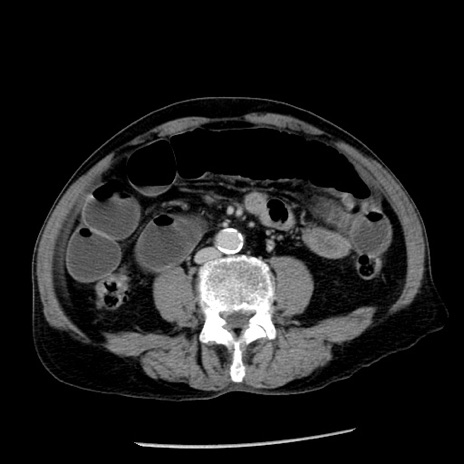

症例26(横断像)

【症例】80歳代男性

【主訴】嘔吐

【現病歴】昨晩2回嘔吐あり、今朝になっても嘔吐あり。来院。

【既往歴】胃潰瘍

【身体所見】意識清明、BT 37.6℃、BP 166/95mmHg、HR 100bpm、SpO2 97%、腹部:平坦・軟、腸蠕動音聴取良好、圧痛なし。

【データ】WBC 21900、CRP 1.46